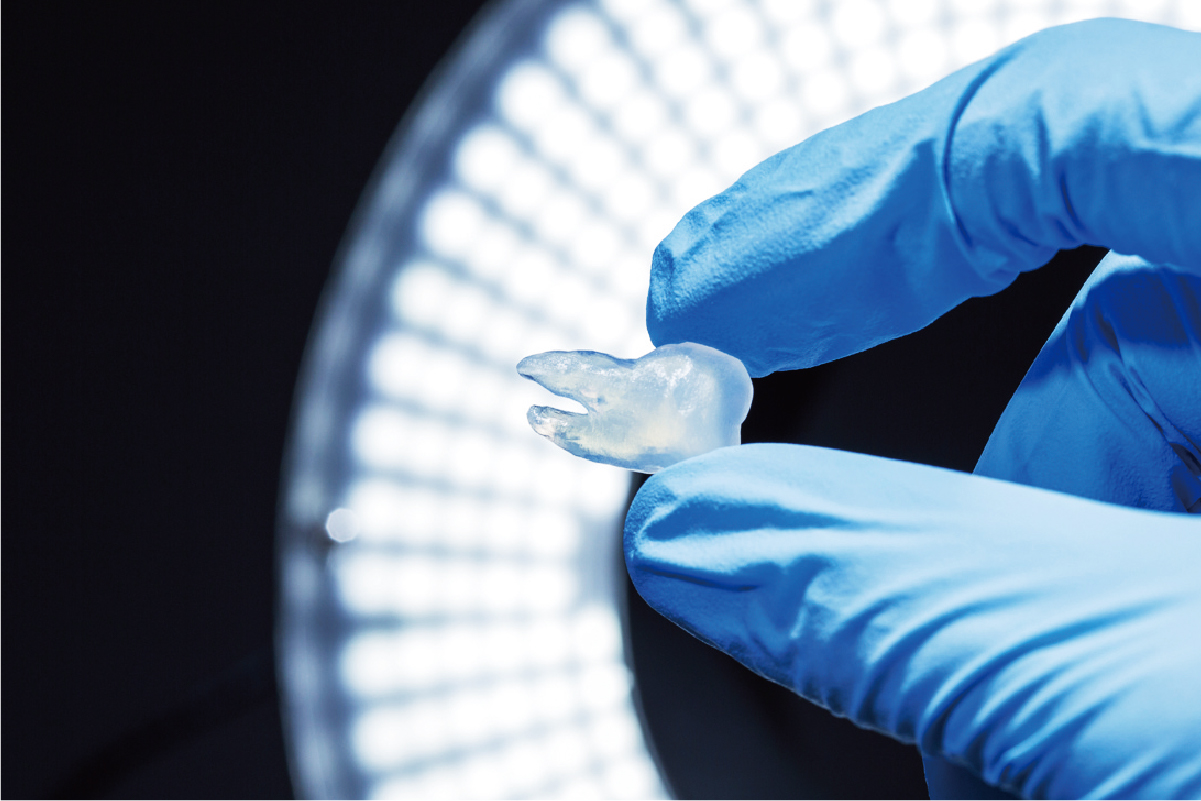

In general, soft models often fail to reproduce some shapes, such as simplifying the inside of organs, but JMC Lab possesses a unique technology that combines 3D printing and casting technologies to faithfully reproduce the outside and inside of organs. JMC Lab has a unique technology that combines 3D printing and casting techniques to faithfully reproduce the outside and inside of organs. This method allows for a higher degree of material flexibility than direct 3D printing of soft materials, and allows for adjustments in hardness, color, X-ray transmission, etc.

Soft organ model

One of the strengths of JMC's medical entity models is the ability to produce soft models. However, JMC's unique know-how and painstaking manufacturing methods enable us to accurately reproduce the complex shapes of organs and to adjust the hardness according to the part to be manufactured. JMC's unique know-how and labor-intensive manufacturing methods enable us to accurately reproduce the complex shapes of organs and adjust the hardness of the parts we manufacture.